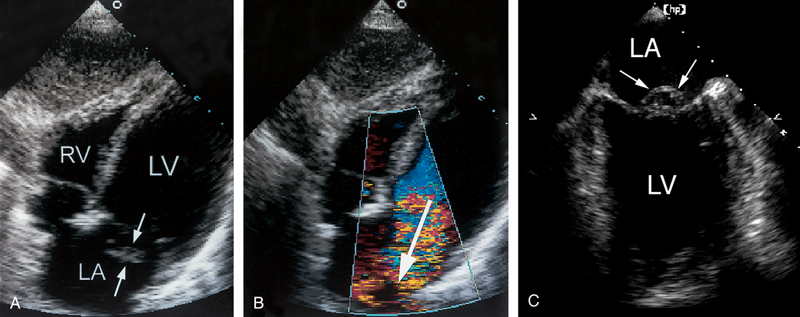

فحوصات تشخيصية لبعض امراض القلب والشرايين التاجية